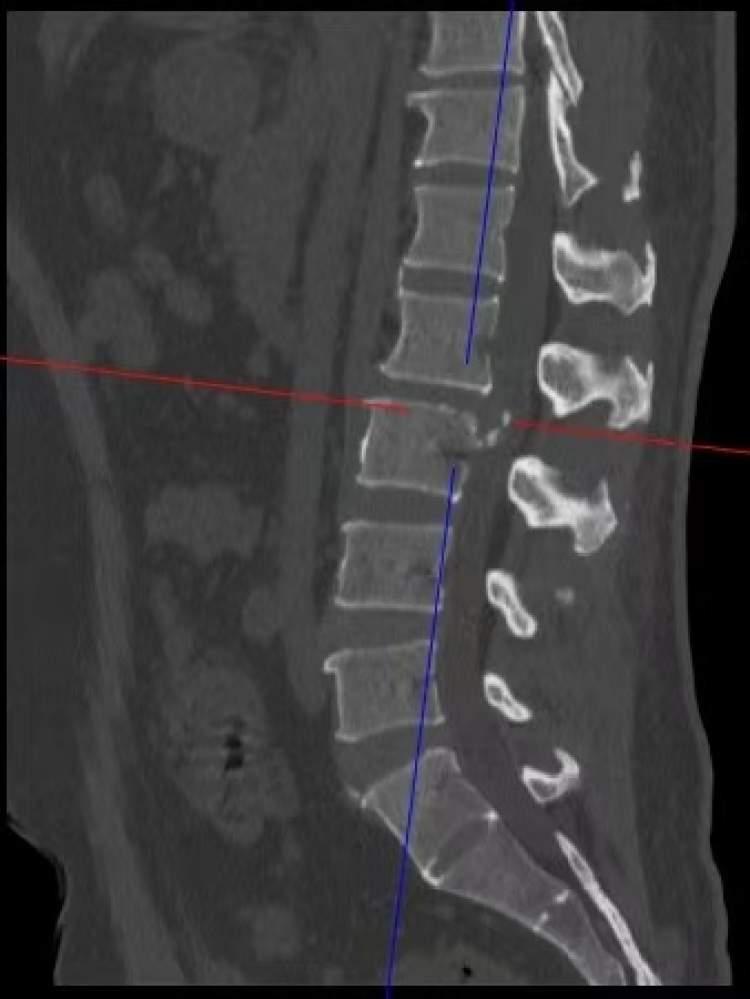

患者入院后,腰椎MRI结果提示:L2-3椎间盘突出,明显钙化,硬膜囊及马尾神经根严重受压,椎管狭窄严重。面对复杂病情,经过多学科讨论,贺石生教授团队决定采用UBD技术实施手术。

与传统手术相比,UBD技术只需1厘米左右的小切口,通过双通道建立,一条通道提供高清可视化视野,另一条通道精准进入病灶区域操作。在毫米级的手术空间内,医生们顺利避开重要神经和血管,清除了压迫硬膜囊及马尾神经根的突出钙化椎间盘组织。

整个手术约1小时,出血量小于50ml,切口1cm,与开放手术需要的20cm切口,大量的出血相比,最大程度避免了对肌肉和骨骼结构的破坏,显著减少了出血。手术后,患者恢复顺利,当天即可自主下床。